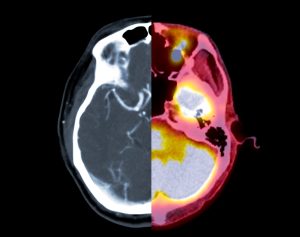

Experiencing CTE symptoms doesn’t automatically mean a person has it. There are a lot of conditions that can cause similar symptoms. A healthcare provider will use tests to help diagnose or rule out these other issues. Tests include:

- CT scan

- MRI

- PET scan